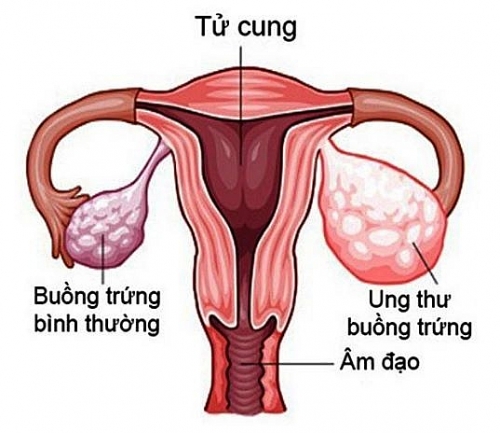

Dấu hiệu nhận biết ung thư buồng trứng

Ung thư buồng trứng là một bệnh gặp ở nữ giới. Nhưng dấu hiệu nhận biết ung thư buồng trứng thế nào và nó có thể di căn ra sao thì không phải ai cũng biết.